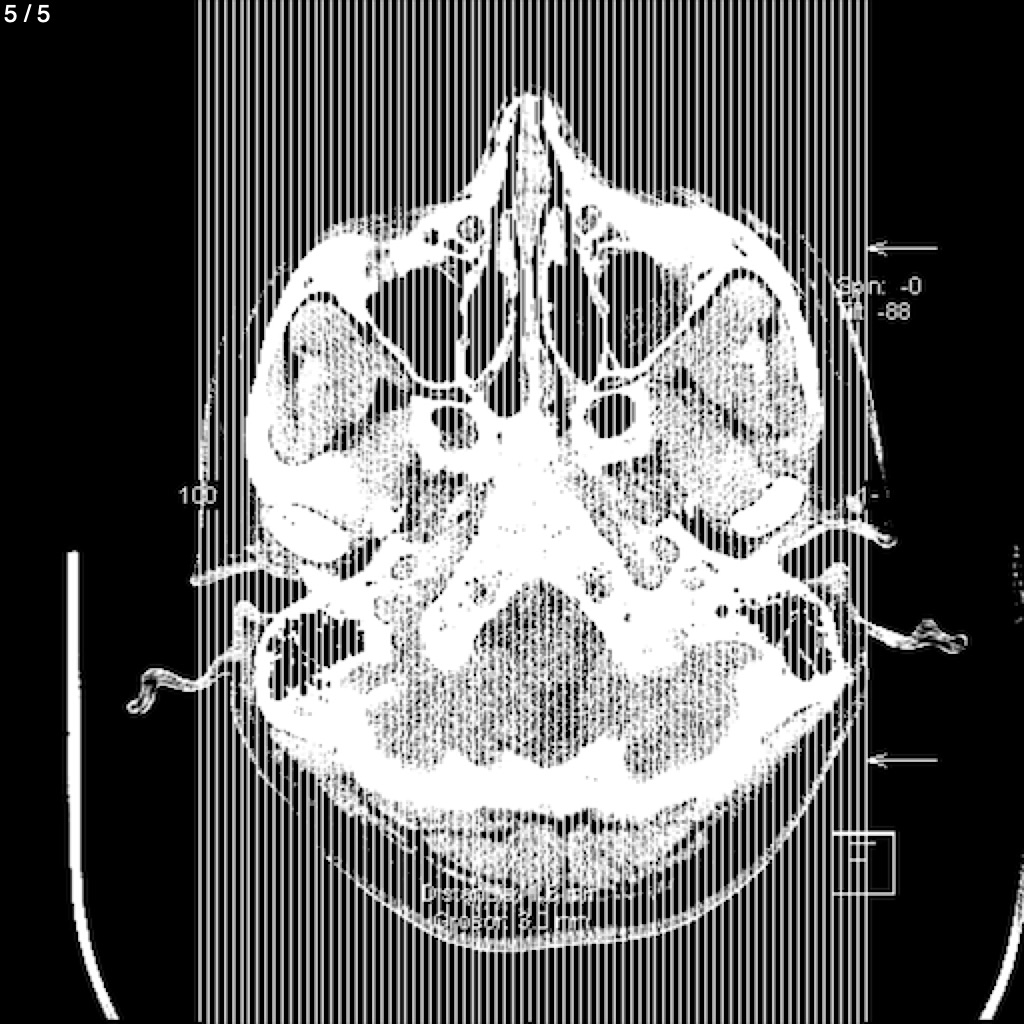

Rufino Eduardo Tovar Lopez - Cabeza Simple_Craneo (Adulto)